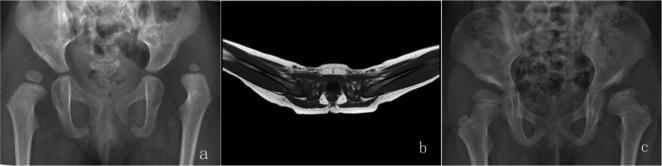

A total of 55 patients (59 hips) with late-detected DDH underwent MRI after CR. Hip abduction angle and hip joint distance were measured on postoperative MRI transverse sections. The acetabular index and centre-edge angle were measured on plain radiographs at the last follow-up. The presence of AVN according to Kalamchi and McEwen's classification was assessed. We retrospectively analyzed the associations among abduction angles, hip joint distances, radiographic parameters, AVN and final outcomes, exploring the relationship between hip joint abduction angle and AVN rate.

The mean age at the time of CR was 14.4 months SD 5.5 (6 to 28), and the mean follow-up was 26.2 months SD 8.1 (12.4 to 41.7). The mean hip abduction angle was 70.2° SD 7.2° (53° to 85°) on the dislocated side and 63.7° SD 8.8° (40° to 82°) on the normal side; the mean hip joint distance was 5.1 mm SD 1.9 (1.3 to 9.1) on the dislocated side and 2.2 mm SD 0.6 on the normal side (1.3 to 3.3). Eight of 59 hips (13.6%) developed AVN. Neither the amount of abduction nor hip joint distance increased the AVN rate (p = 0.97 and p = 0.65, respectively) or the dislocation rate (p = 0.38 and p = 0.14, respectively).

Abduction angle up to 70.2° following CR did not increase the AVN rate in children aged six to 28 months with late-detected DDH treated by CR.